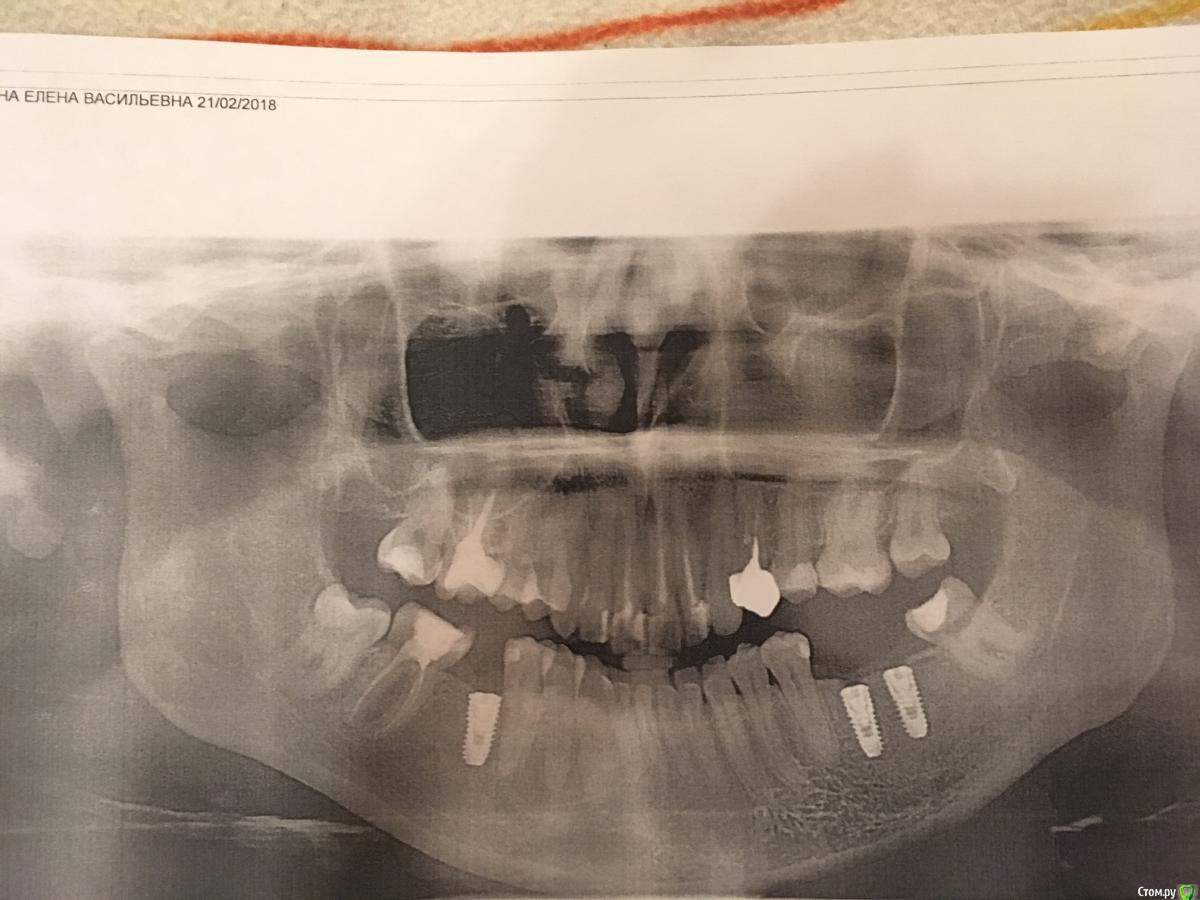

evaverkina Опубликовано 21 февраля, 2018 Поделиться Опубликовано 21 февраля, 2018 (изменено) Добрый вечер всем. Установили 3 импланта 10 февраля 2018г. Сегодня сделала панорамный снимок, имплант очень близко к зубу 45, зуб начал побаливать. Болит при постукивании. Доктор утверждает что все хорошо. Допустимо ли такое расположение импланта к зубу? Есть ли вероятность что имплант затронул зуб? Изменено 21 февраля, 2018 пользователем evaverkina Ссылка на комментарий

red_butler Опубликовано 22 февраля, 2018 Поделиться Опубликовано 22 февраля, 2018 Сделайте Кт 1 Ссылка на комментарий

evaverkina Опубликовано 22 февраля, 2018 Автор Поделиться Опубликовано 22 февраля, 2018 (изменено) Фото КТ Изменено 22 февраля, 2018 пользователем evaverkina Ссылка на комментарий

evaverkina Опубликовано 22 февраля, 2018 Автор Поделиться Опубликовано 22 февраля, 2018 Сделайте Кт Фото КТ прикрепила, есть возможность отправить вам КТ целиком или этого достаточно? Ссылка на комментарий